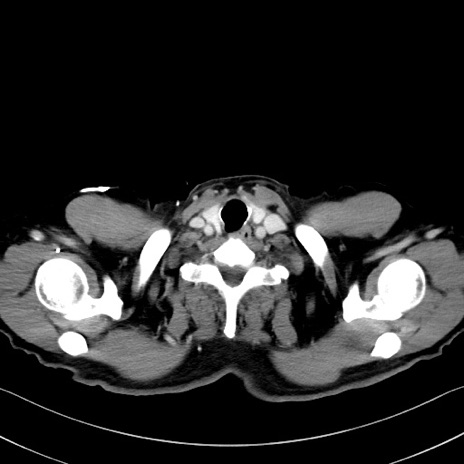

症例35(横断像)

【症例】70歳代 男性

【主訴】腹部膨満、嘔吐

【現病歴】昨日より腹部膨満感出現。本日増悪し、仙痛出現。嘔吐あり、受診。

【既往歴】糖尿病、胆摘後

【身体所見】BP 149/80mmHg、HR 74/min、BT 35.9℃、腹部:膨満、軟、圧痛なし。腸雑音減弱あり。上腹部正中切開瘢痕あり。

【データ】WBC 13500、CRP 1.72